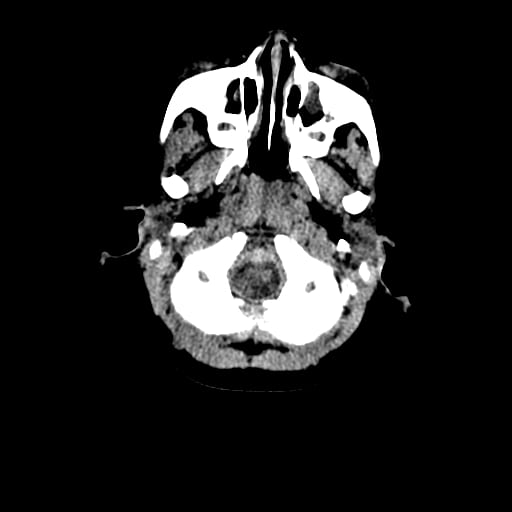

Age: 1

Sex: Male

Indication: Fall